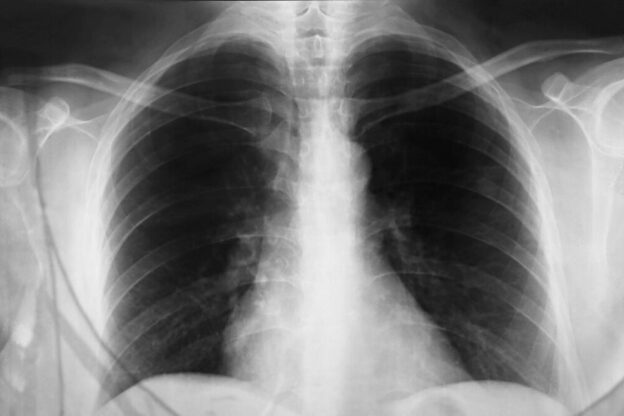

Stručnjaci ističu da kašalj, bez obzira na uzrok, ne bi trebao trajati duže od tri sedmice. Ukoliko se to dogodi, savjetuje se detaljniji pregled disajnih puteva, posebno pluća, kako bi se na vrijeme isključili ozbiljniji zdravstveni problemi. Rano otkrivanje uzroka ključno je za uspješno liječenje i sprječavanje daljih komplikacija.

Ljekari naglašavaju da se dugotrajan, neuobičajen ili sve jači kašalj ne smije ignorirati. Posebnu pažnju treba obratiti ako se pojave dodatni simptomi poput zviždanja u grudima, osjećaja nedostatka zraka ili bola u prsima. Pravovremeni pregled i stručan savjet mogu spriječiti razvoj ozbiljnijih problema.